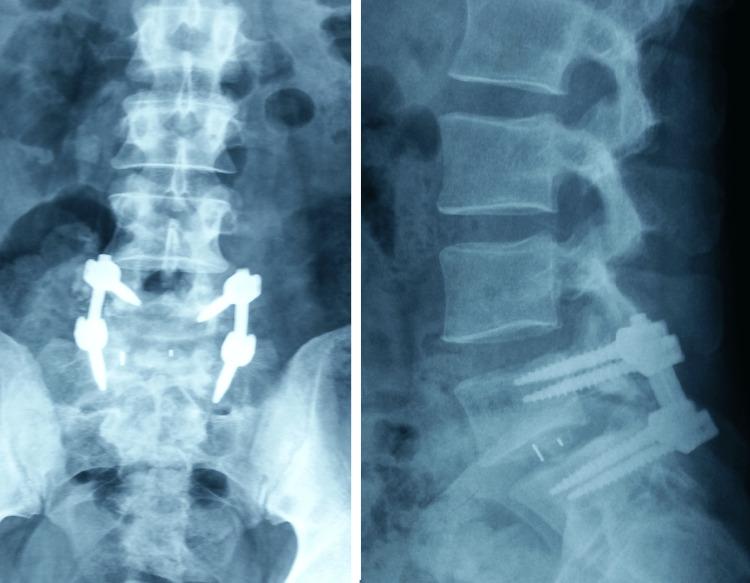

Traumatic dislocation of the lumbosacral joint is a rare and severe lesion usually caused by high-energy trauma. The literature on traumatic spondylolisthesis is limited, and most published papers are sporadic case reports. By presenting the case of an anterior traumatic L5-S1 spondylolisthesis without neurological deficits caused by a 6-meter fall, we discuss the anatomopathological mechanism of this injury, clinical and radiological evaluation, and current management options. The patient was treated surgically with a combined posterior instrumented reduction and transforaminal interbody fusion. At the final follow-up after seven years, the radiological evaluation showed an unchanged spondylolisthesis reduction with reliable fusion healing. In addition, the patient had good functional results and resumed recreational activities and work. Traumatic lumbosacral spondylolisthesis requires a careful and well-documented initial clinical and radiological assessment. Most authors advocate surgical treatment as the mainstay of management. However, the long-term prognosis remains unclear and unpredictable.

腰骶关节创伤性脱位是一种罕见且严重的损伤,通常由高能量创伤引起。关于创伤性腰椎滑脱的文献有限,大多数已发表的论文都是散发性病例报告。通过呈现一例因6米高处坠落导致的无神经功能缺损的前侧创伤性L5-S1腰椎滑脱病例,我们讨论了这种损伤的解剖病理机制、临床和影像学评估以及当前的治疗选择。该患者接受了后路器械辅助复位联合经椎间孔椎间融合的手术治疗。在七年的最终随访中,影像学评估显示腰椎滑脱复位情况未变,融合愈合可靠。此外,患者功能恢复良好,恢复了娱乐活动和工作。创伤性腰骶部腰椎滑脱需要进行仔细且记录完善的初始临床和影像学评估。大多数作者主张手术治疗作为主要的治疗方法。然而,长期预后仍不明确且难以预测。